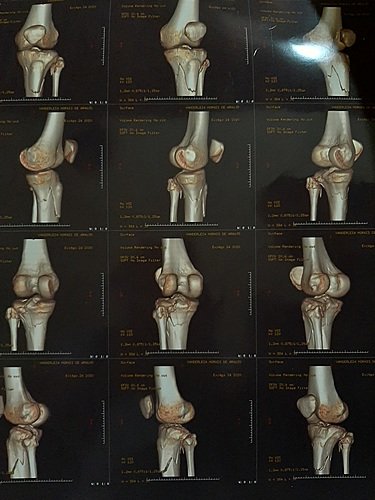

Oi, meu nome é Vanderleia Morais De Araújo tenho 25 anos, moro em Camocim Ceará. No dia 20 de agosto de 2020 sofri um acidente de moto que ocasionou fraturas complexas na minha perna esquerda, comprometendo a articulação do joelho, fazendo com que eu necessite de uma cirurgia em caráter de urgência na tíbia (Osteossítese) + duas placas bloqueadas com parafusos bloqueados. Cirugia avaliada em R$ 13. 200,00